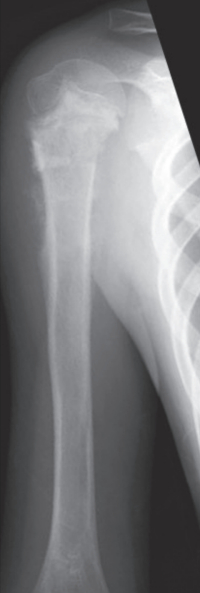

血液所見:赤血球 468万、Hb 13.9 g/dL、白血球 4,300、血小板 18万。血液生化学所見:総蛋白 7.5 g/dL、アルブミン 3.9 g/dL、総ビリルビン 0.9 mg/dL、直接ビリルビン0.2mg/dL、AST 28 U/L、ALT 16 U/L、LD 177 U/L(基準 120~245)、ALP 566 U/L(基準 38~113)、γ-GT 32 U/L(基準 8~50)、CK 42 U/L(基準 30~140)、尿素窒素 12 mg/dL、クレアチニン 0.3 mg/dL、尿酸 4.9 mg/dL、Na 136 mEq/L、K 4.4 mEq/L、Cl 97 mEq/L。CRP 0.9 mg/dL。右上腕骨の単純エックス線写真とMRIの脂肪抑制造影T1強調冠状断像を別に示す。